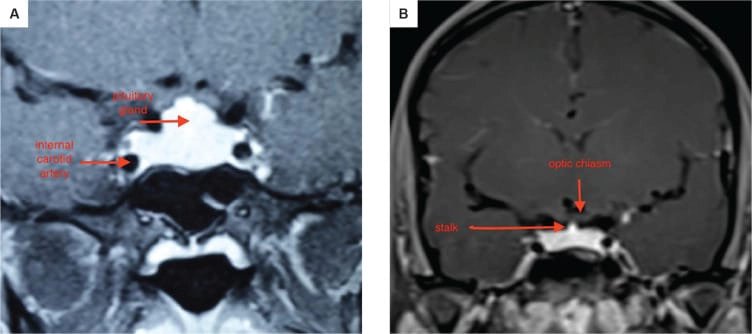

১. অবস্থান ও গঠন: পিটুইটারি গ্রন্থি একটি হাড়ের গঠন, যাকে সেলা টার্সিকা বলা হয়, তার ভিতরে বসে থাকে। এটি মাথার খুলির নিচের দিকে, স্ফেনয়েড নামক হাড়ে একটি গহ্বর, যা নাকের পেছনে অবস্থান করে। এটি অপটিক কায়াজম (optic chiasm) এর নিচে অবস্থিত, যেখানে দুটি চোখের স্নায়ু পরস্পর ক্রস করে। এটি ইন্টারনাল ক্যারোটিড আর্টারি নামক দুটি প্রধান রক্তনালীর মাঝখানে থাকে।